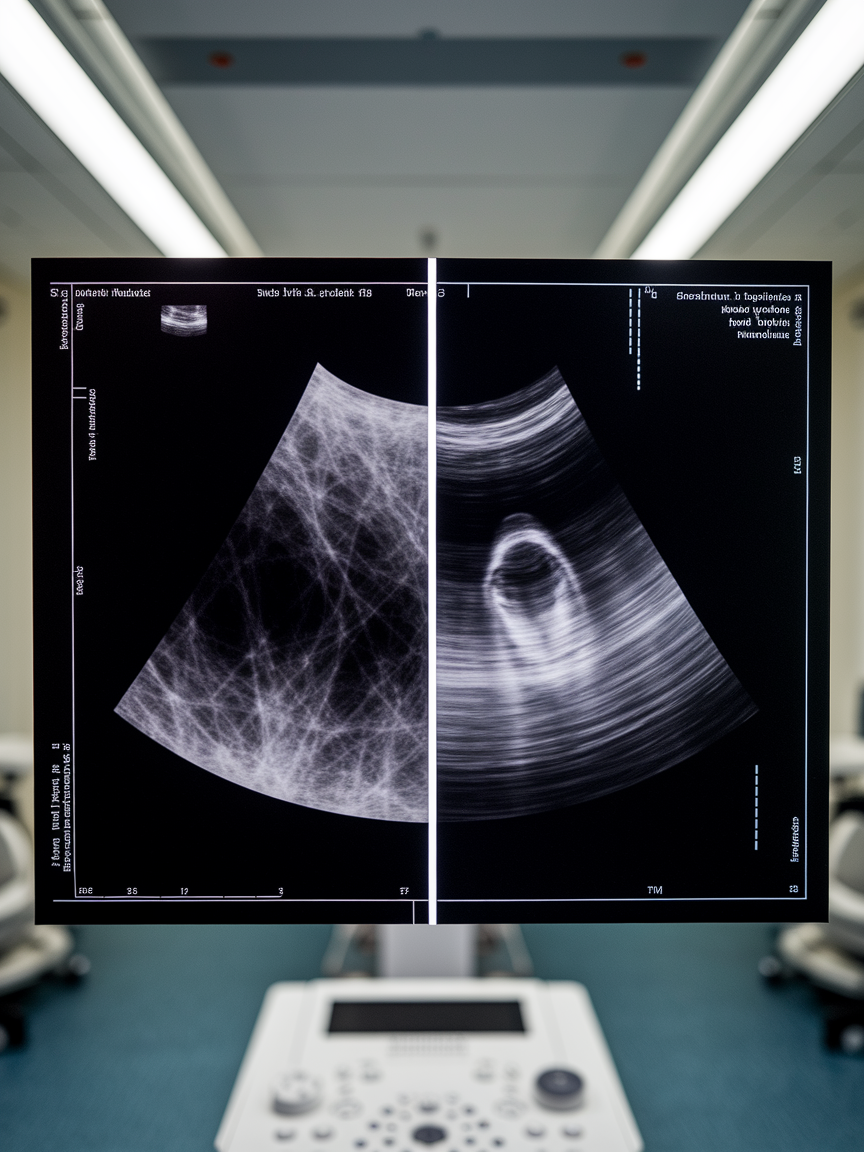

유방암 검진 방법으로 가장 많이 사용되는 것이 유방 촬영술(맘모그램)과 유방 초음파예요. 두 가지 검사법은 각기 다른 특징을 가지고 있어서, 개인의 상황에 맞게 선택하는 것이 중요해요.

맘모그램은 유방을 X-ray로 촬영하는 방식이에요. 특히 40세 이상의 여성들에게 추천되는데, 유방 조직이 지방보다 섬유 조직이 많을 경우에는 병변을 찾기 어려울 수도 있어요. 반면, 유방 초음파는 고주파 음파를 이용해 혹의 크기와 모양을 보다 명확하게 확인할 수 있어요.

치밀유방을 가진 여성들은 맘모그램에서 정확한 판독이 어려울 수 있기 때문에 초음파 검사가 추가로 필요할 수도 있어요. 하지만 유방 초음파만으로는 미세 석회화 등의 병변을 찾기가 어렵기 때문에 두 검사를 병행하는 것이 가장 효과적이에요.

따라서 40세 이상의 여성은 기본적으로 맘모그램을 받되, 유방 조직이 치밀하거나 가족력이 있는 경우 초음파를 병행하는 것이 좋아요. 💡